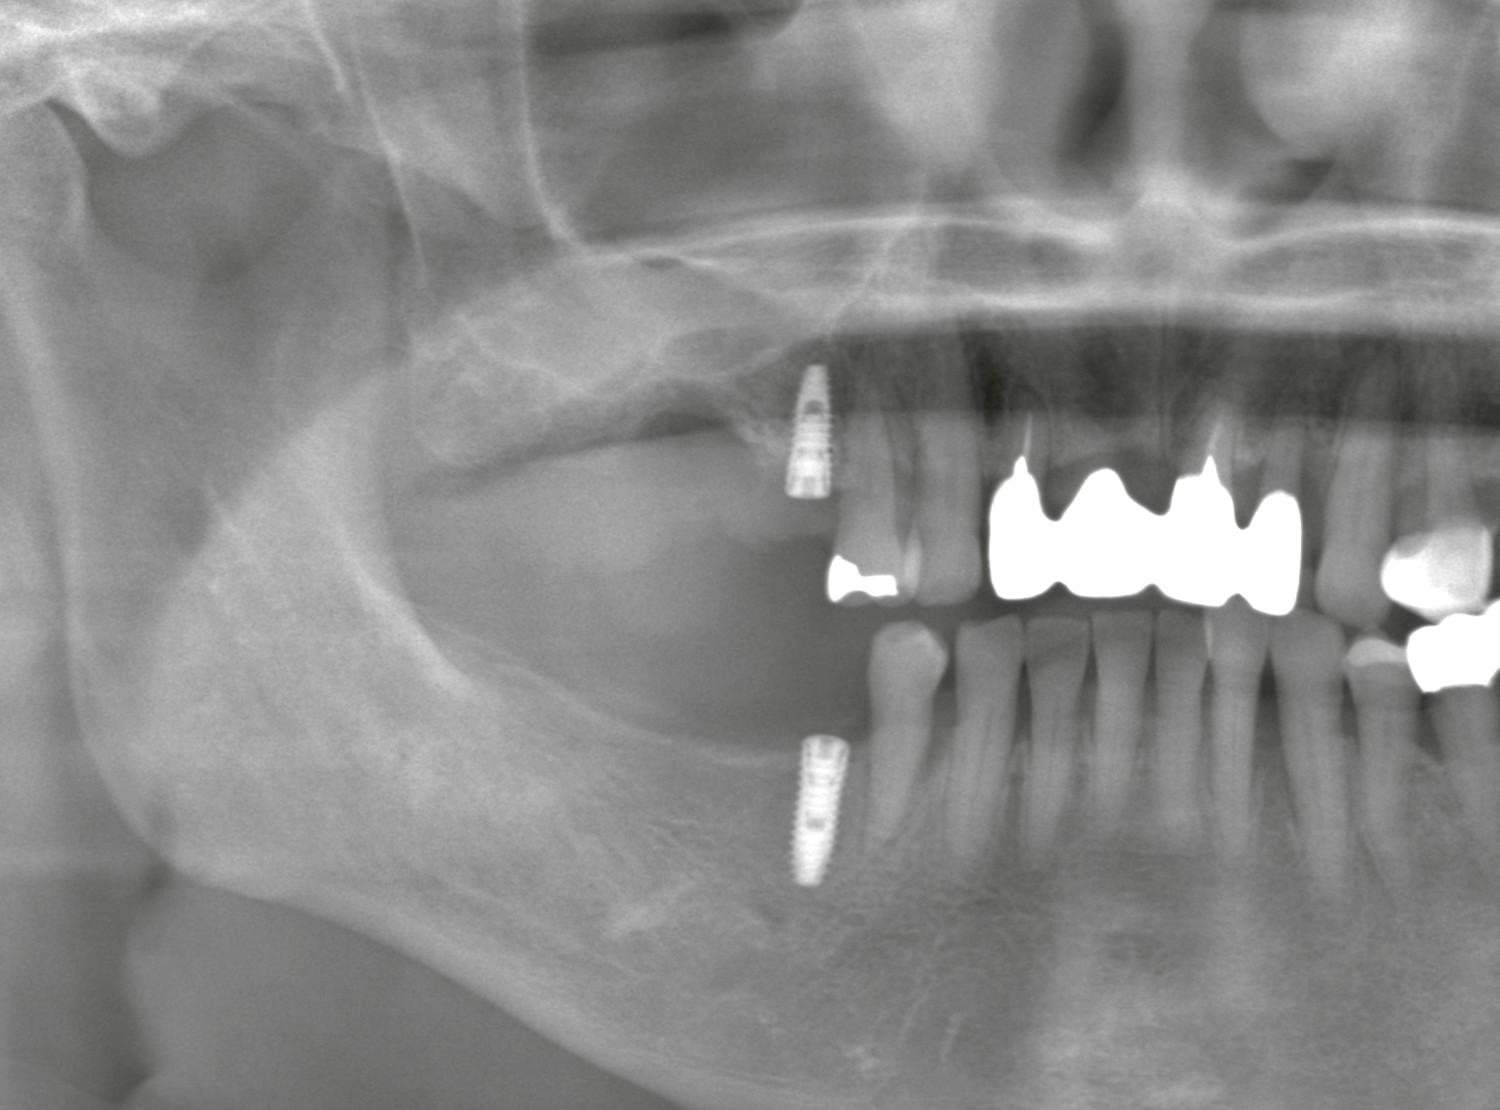

昨日は、右側の上下にインプラント治療を行いました。

そのうち1本は「抜歯即時インプラント」(抜歯と同日にインプラントを埋入する方法)で実施しています。